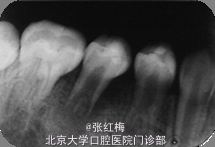

在牙髓再生术后1个月,3个月,5个月,9个月复查 1个月x线:45根尖周低密度影缩小,牙根继续发育。 3个月x线:45根尖周未见病变影,根周膜清晰,牙根继续发育。 5个月x线:45根尖周未见病变影,根周膜清晰,牙根继续发育。 9个月x线:45根尖周未见病变影,根周膜清晰,牙根继续发育,已近完成,髓腔缩小。 讨论:由于畸形中央尖一部分有髓角伸入,因此发现畸形中央尖应根据不同情况给予及时或相应处理。对于圆钝而无妨碍的中央尖可以不做处理。尖而长的中央尖容易折断或被磨损而露髓.可在麻醉和严格消毒下将此尖一次磨除。制备洞形,盖髓充填。还有一种方法树脂在牙尖周围加固防折,使畸形尖随牙齿一同发生生理磨耗,促使髓角形成修复性牙本质,可用于尚未建合的牙。短期内折断的畸形中央尖无牙髓根尖炎症状,且牙髓活力正常者,备洞盖髓充填。折断的畸形中央尖有牙髓炎根尖炎者,往往牙根未发育完成,需做根尖诱导形成术,或牙髓再生治疗。 牙髓坏死或者根尖炎年轻恒牙的牙髓治疗方法有:根尖诱导成形术,MTA根尖封闭技术,近年来的牙髓再生技术。 根尖诱导成形术,所用根管内充填材料是氢氧化钙及其制剂,诱导根尖周的组织在根尖部形成钙化屏障。需要多次复诊和更换根充药物,疗程较长,增加了根管再次污染的可能性,并不是所有都能形成根尖部的钙化封闭。而且根管壁仍然薄弱,增加了远期根折的风险。 MTA具有良好的生物相容性和封闭性,MTA根尖封闭技术中用其特性封闭根尖,防止充填材料在根尖部的外溢。生物相容性好,可以诱导矿化,但其完全固化需要较长时间,不易操作,抗菌效果不确定,价格昂贵。 牙髓血管再生术通过在操作中彻底有效的根管消毒,尽量保护牙髓干细胞和牙乳头间充质干细胞,并为这些干细胞的增殖和分化提供良好的环境,这些干细胞在信号分子和盖髓剂矿物三氧化物凝聚体(mineral trioxide aggregate,MTA)的诱导下,可以分化为成牙本质细胞和成牙骨质细胞等,从而在牙根继续发育中发挥着重要作用。研究表明,在坏死感染的年轻恒牙根管内进行成功的血管再生后,其根尖周炎症能愈合且牙根得以持续发育,出现根尖闭合、根管长度增加及管壁增厚等,牙髓血管再生术有可能成为治疗年轻恒牙根尖周炎的新选择。